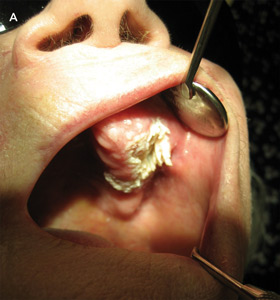

On examination, the location, and surface and subepithelial characteristics of lesions are important factors in diagnosis2,3 (see diagnostic algorithm, Box 2). White lesions in high-risk areas, such as the ventral surface of the tongue and floor of the mouth, have a high propensity for neoplastic change. Surface debris that is easily wiped off suggests candidiasis, while a speckled white patch that cannot be rubbed off is potentially precancerous, carcinoma in situ or squamous cell carcinoma. A homogeneous, striated white patch with no evidence of surface breach is likely to be benign (Box 3 A). Lesions may have a warty surface (Box 1 A). Verrucoid-papillary leukoplakia (verrucous hyperplasia), characterised by an irregular exophytic wart-like appearance, has been reported to be premalignant and has the potential to spread locally.4 Lesions may show temporal progression. Early leukoplakia presents as a faint, slightly elevated white plaque, but it can progress to a thicker and whiter lesion with development of a leathery appearance and fissuring surface.

Leukoplakia is a clinical term traditionally used to describe an oral white lesion that cannot be rubbed off or characterised as any other definable lesion.5 More recently, it was redefined as a predominantly white lesion with premalignant potential.6 It is the most common clinical diagnosis of oral white lesions,7 but does not have a histological basis. Lesions with surface irregularities are referred to as granular or nodular leukoplakia, and those with papillary surfaces as verrucous leukoplakia.8